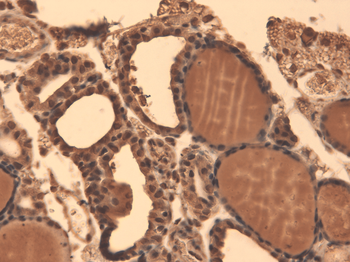

IHC-P image of human thyroid cancer tissue using NIS antibody (2.5 ug/ml)

Immunohistochemical staining of paraffin embedded mouse ovary tissue using NIS antibody (2.5 ug/ml)